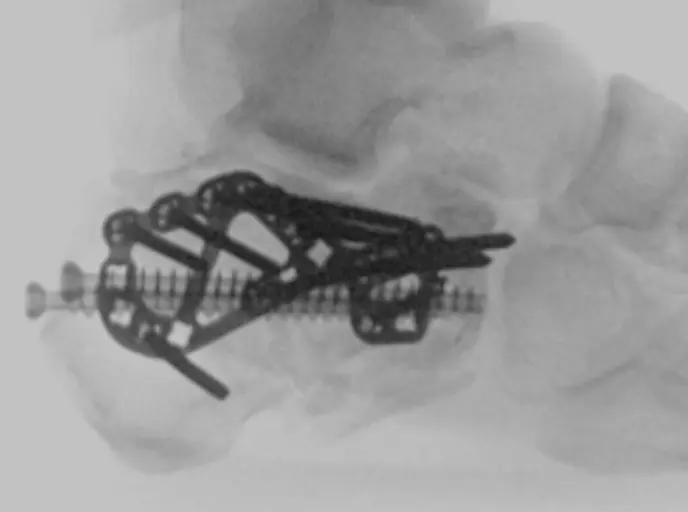

Combined surgical fixation acetabulum and total hip for geriatric acetabulum fracture

Combined surgical fixation acetabulum and total hip for geriatric acetabulum fracture